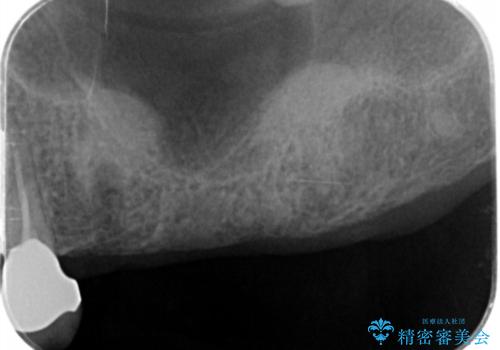

3本の歯(クラウン)を2本のインプラントで支えるインプラントブリッジによる咬合機能の回復を計画します。

また十分な骨の厚みを確保するためソケットリフト法を併用し、長期的な安定を見込めるインプラント治療を実践します。